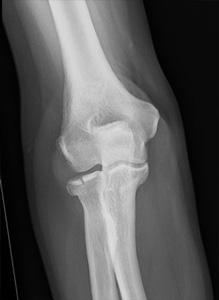

Fracture de la palette humérale

Une ostéosynthèse stable par plaques est souvent nécessaire. Le montage doit être stable pour permettre la rééducation immédiate afin de lutter contre l’enraidissement articulaire.

Fracture de la tête radiale

le traitement diffère selon les stades, en fonction du déplacement et du nombre de fragment.

On distingue le traitement fonctionnel pour les fractures peu déplacées : écharpe coude au corps à visée antalgique à 10 jours et mobilisation précoce du coude.

Et le traitement chirurgical pour les fractures déplacées : ostéosynthèse par vis enfouies, plaque ; ou remplacement de la tête radiale par une prothèse dans les cas où la tête radiale n’est pas réparable.

Fracture de l’olécrane

En plus de la fracture articulaire, la fracture de l’olécrane correspond à une interruption de l’appareil extenseur du coude. Les fractures déplacées nécessitent une ostéosynthèse adaptée à la fracture : par broches et hauban, par ostéo suture ou par plaque vissée en fonction de l’âge, de la qualité osseuse et de la taille des fragments.